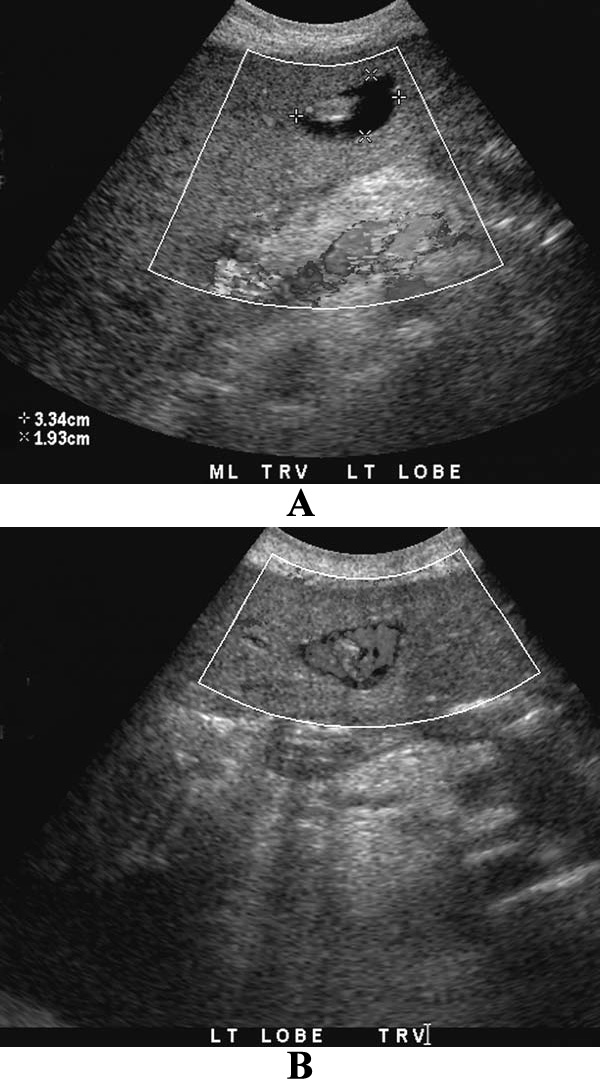

УЗИ почек: артефакт мерцания при камнях в почках

Фото 2. УЗИ почек: артефакт мерцания при камнях в почках. А – черно-белое изображение демонстрирует слабый эхогенный очаг в нижнем полюсе почки и еще один очаг – в верхнем полюсе почки. Эти очаги сложно отличить от синуса. Тени отсутствуют. В – цветное допплеровское исследование демонстрирует интенсивное мерцание (разноцветные пиксели) позади камней, также наблюдается нормальный цвет потока почечных сосудов. Камни в почках трудно диагностировать без обнаружения мерцания